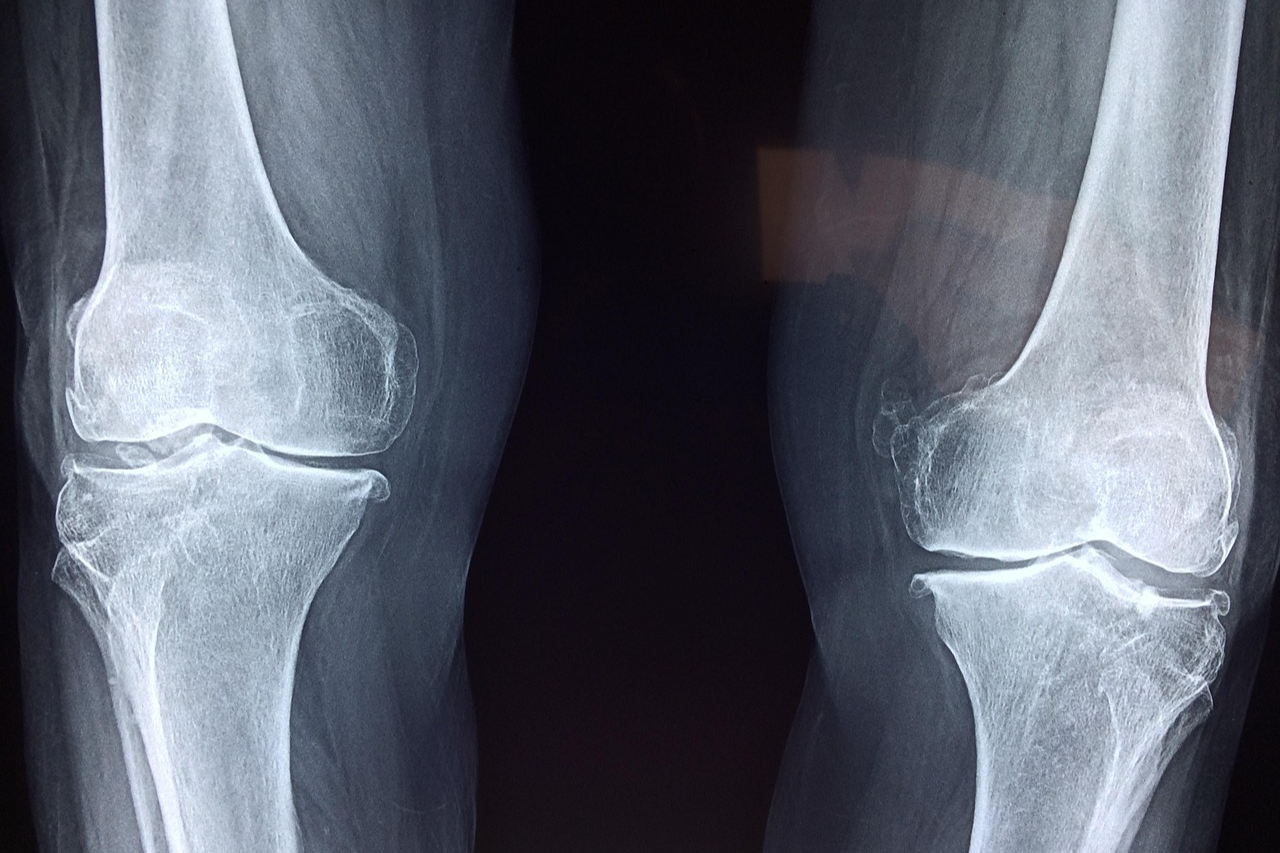

🔹 X-ray 촬영 후 골절 상태 확인

🩺 골절의 종류와 특징

골절의 형태에 따라 치료 방법이 달라지므로 정확한 진단과 치료가 필수적입니다.